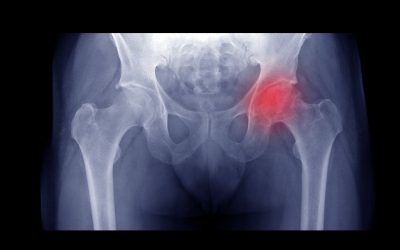

Avaskularna nekroza ili osteonekroza je odumiranje koštanog tkiva zbog nedostatka prokrvljenosti. Ovo stanje može dovesti do malih lomova u strukturi i kolapsa kosti. Svatko može oboljeti od avaskular